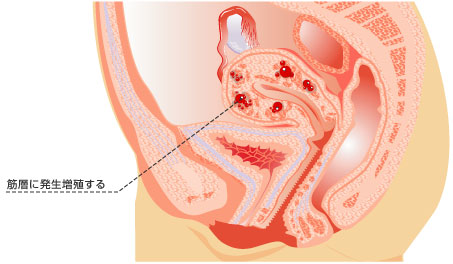

子宮筋腫は子宮の筋層の中にできる良性の腫瘍で、筋肉でできたこぶのようなものです。子宮筋腫の代表的な症状は、月経の量が多い、生理痛が強い、赤ちゃんができにくいといったことです。

しかし、子宮筋腫の症状の強さは筋腫の大きさや位置によって千差万別です。子宮筋腫があっても子宮の外側にりんごのように突き出しているものならかなり大きな筋腫でも全く症状がなく、妊娠にも影響がない場合もあります。逆に小さな筋腫でも子宮の内側に突き出している筋腫は、月経の量が多く、生理痛も強い場合が多いようです。筋腫が子宮の内側に張り出してくると子宮の内側がでこぼこになって、せっかく受精しても受精卵が子宮の内側に取り付くことができなくなり、不妊症になってしまいます。

子宮の内側の膜にある腺組織が本来あるべきではない子宮の筋層の中にあることによって起こる病気です。月経のたびに出血しますが、出ていくところがないので溜まってしまいます。月経痛が強いのが特徴です。 子宮の内側の膜にある腺組織が本来あるべきではない子宮の筋層の中にあることによって起こる病気です。月経のたびに出血しますが、出ていくところがないので溜まってしまいます。月経痛が強いのが特徴です。